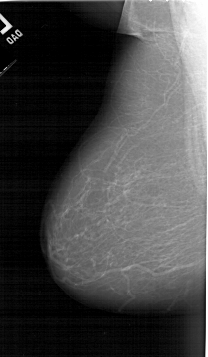

A_1255_1.RIGHT_MLO

A_1255_1.RIGHT_CC

RIGHT_CC LINES 6571 PIXELS_PER_LINE 3736 BITS_PER_PIXEL 12 RESOLUTION 43.5 OVERLAY

RIGHT_MLO LINES 6241 PIXELS_PER_LINE 3766 BITS_PER_PIXEL 12 RESOLUTION 43.5 OVERLAY